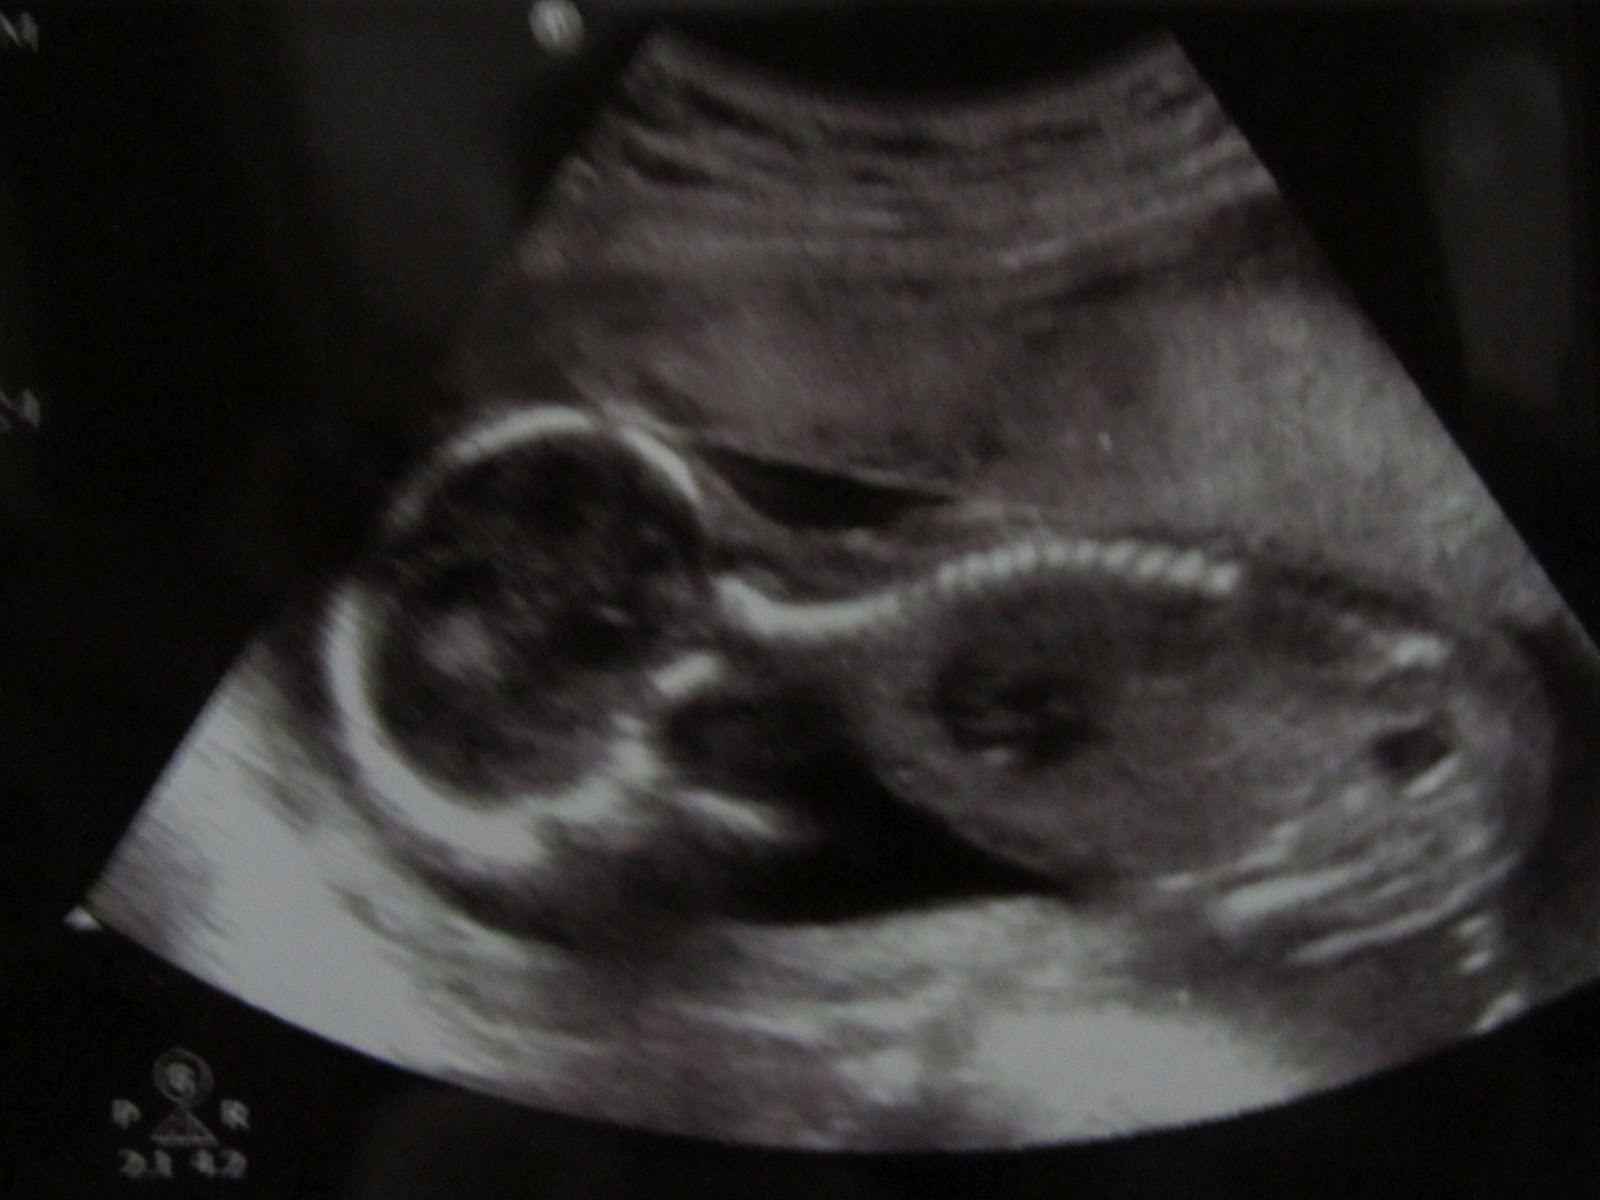

We're Having a Boy!!

Jeff and I are excited to announce that our little one is a boy! We had our appointment August 3rd and we are happy to say that everything looks great so far. I cannot begin to explain the emotions I felt seeing our baby while getting our ultrasound. It took everything I had to not giggle the whole time! We were happy to see the heart (all 4 chambers-amazing!), the brain, the nose, eyes, mouth, the kidneys, the spinal cord, his little legs and arms, and we could even see his fingers! The best part of all was seeing Jeff's face when she showed us the boy parts! :)

We did find out at this appointment that our little guy is smaller than to be expected. The doctors were thinking I was 20 (well a day away from 21) weeks and due around December 16th. The ultrasound however, shows that I am just now 19 weeks and the baby is actually due December 28th. We will not know for sure though until my second ultrasound in September. At this point they will measure the baby again and hopefully have a better idea of when I am due.